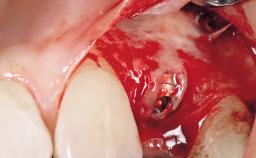

Late Placement of an Implant in a Maxillary Left Central Incisor Site

A 30-year-old female patient had lost tooth 21 and was referred to our clinic for consultation and treatment. Due to advanced apical infection, tooth 21 had been extracted two months earlier at another clinic and an acrylic-resin tooth had been bonded to the adjacent teeth. The patient desired implant treatment to avoid any damage to the adjacent natural teeth. While the patient had no history of any systemic disorder, she was a heavy smoker and exhibited medium to advanced periodontitis in the entire jaw. After the initial treatment to achieve a pocket probing depth of less than 4 mm and no bleeding on probing, a decrease in the height of the papillae mesial and distal to the extraction site and overall gingival recession were observed.